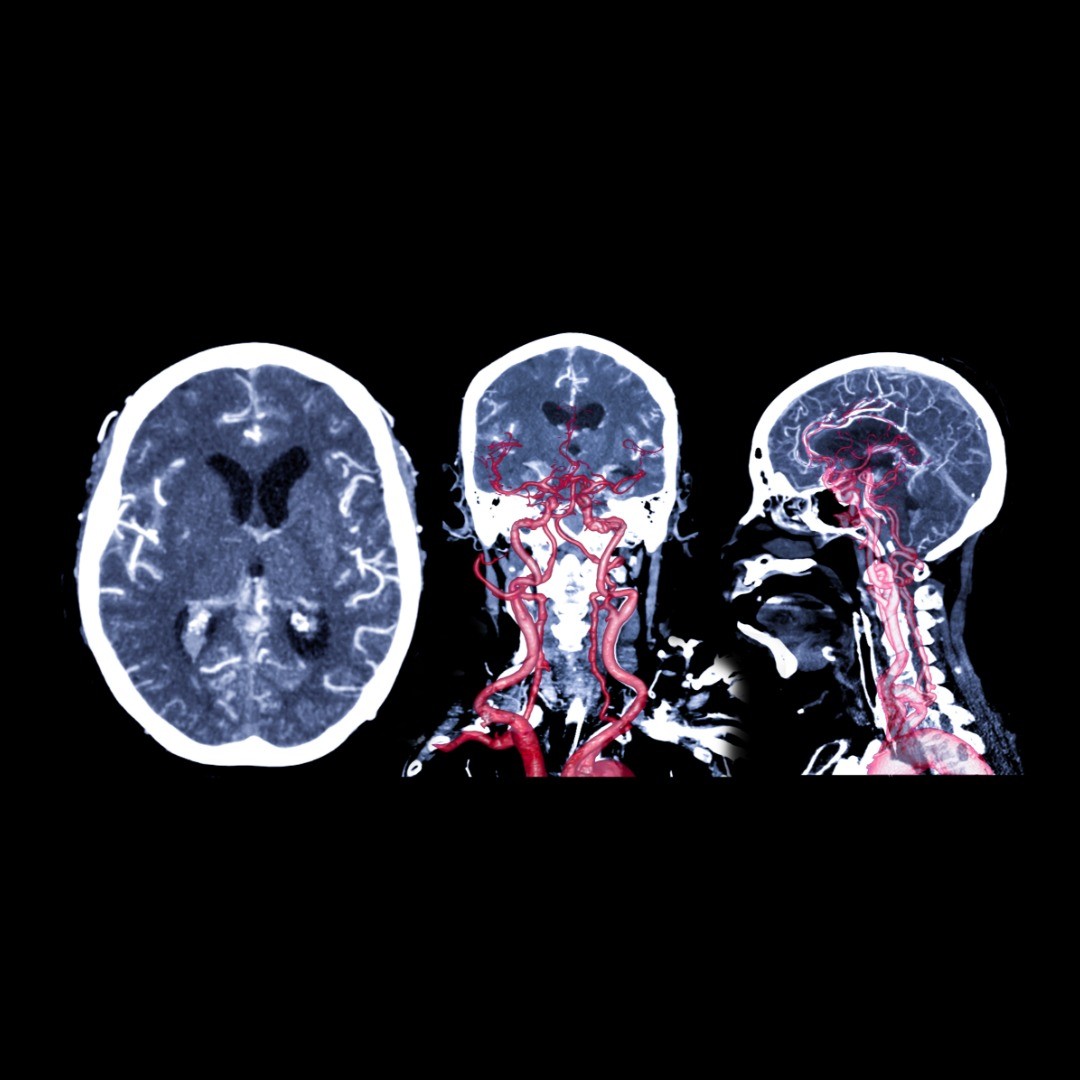

A brain aneurysm, also known as a cerebral aneurysm, is a weak area in the blood vessel wall of the brain. An aneurysm can balloon and then rupture or leak, causing a stroke.